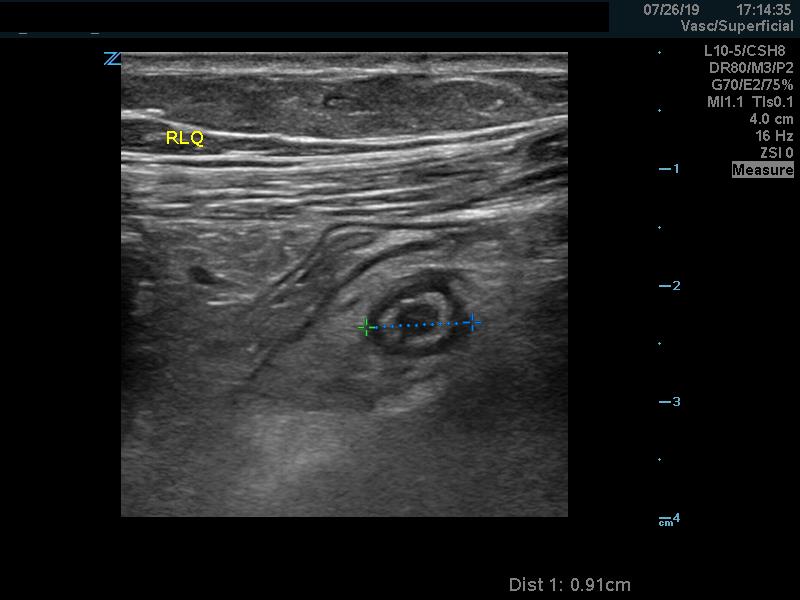

Diagnostic criteria: Appendix measuring more than 6 mm in transverse diameter under compression (98% Sens)1

Figure 5. Dilated, non-compressible appendix.

Video 3. Dilated, non-compressible appendix (compression applied).